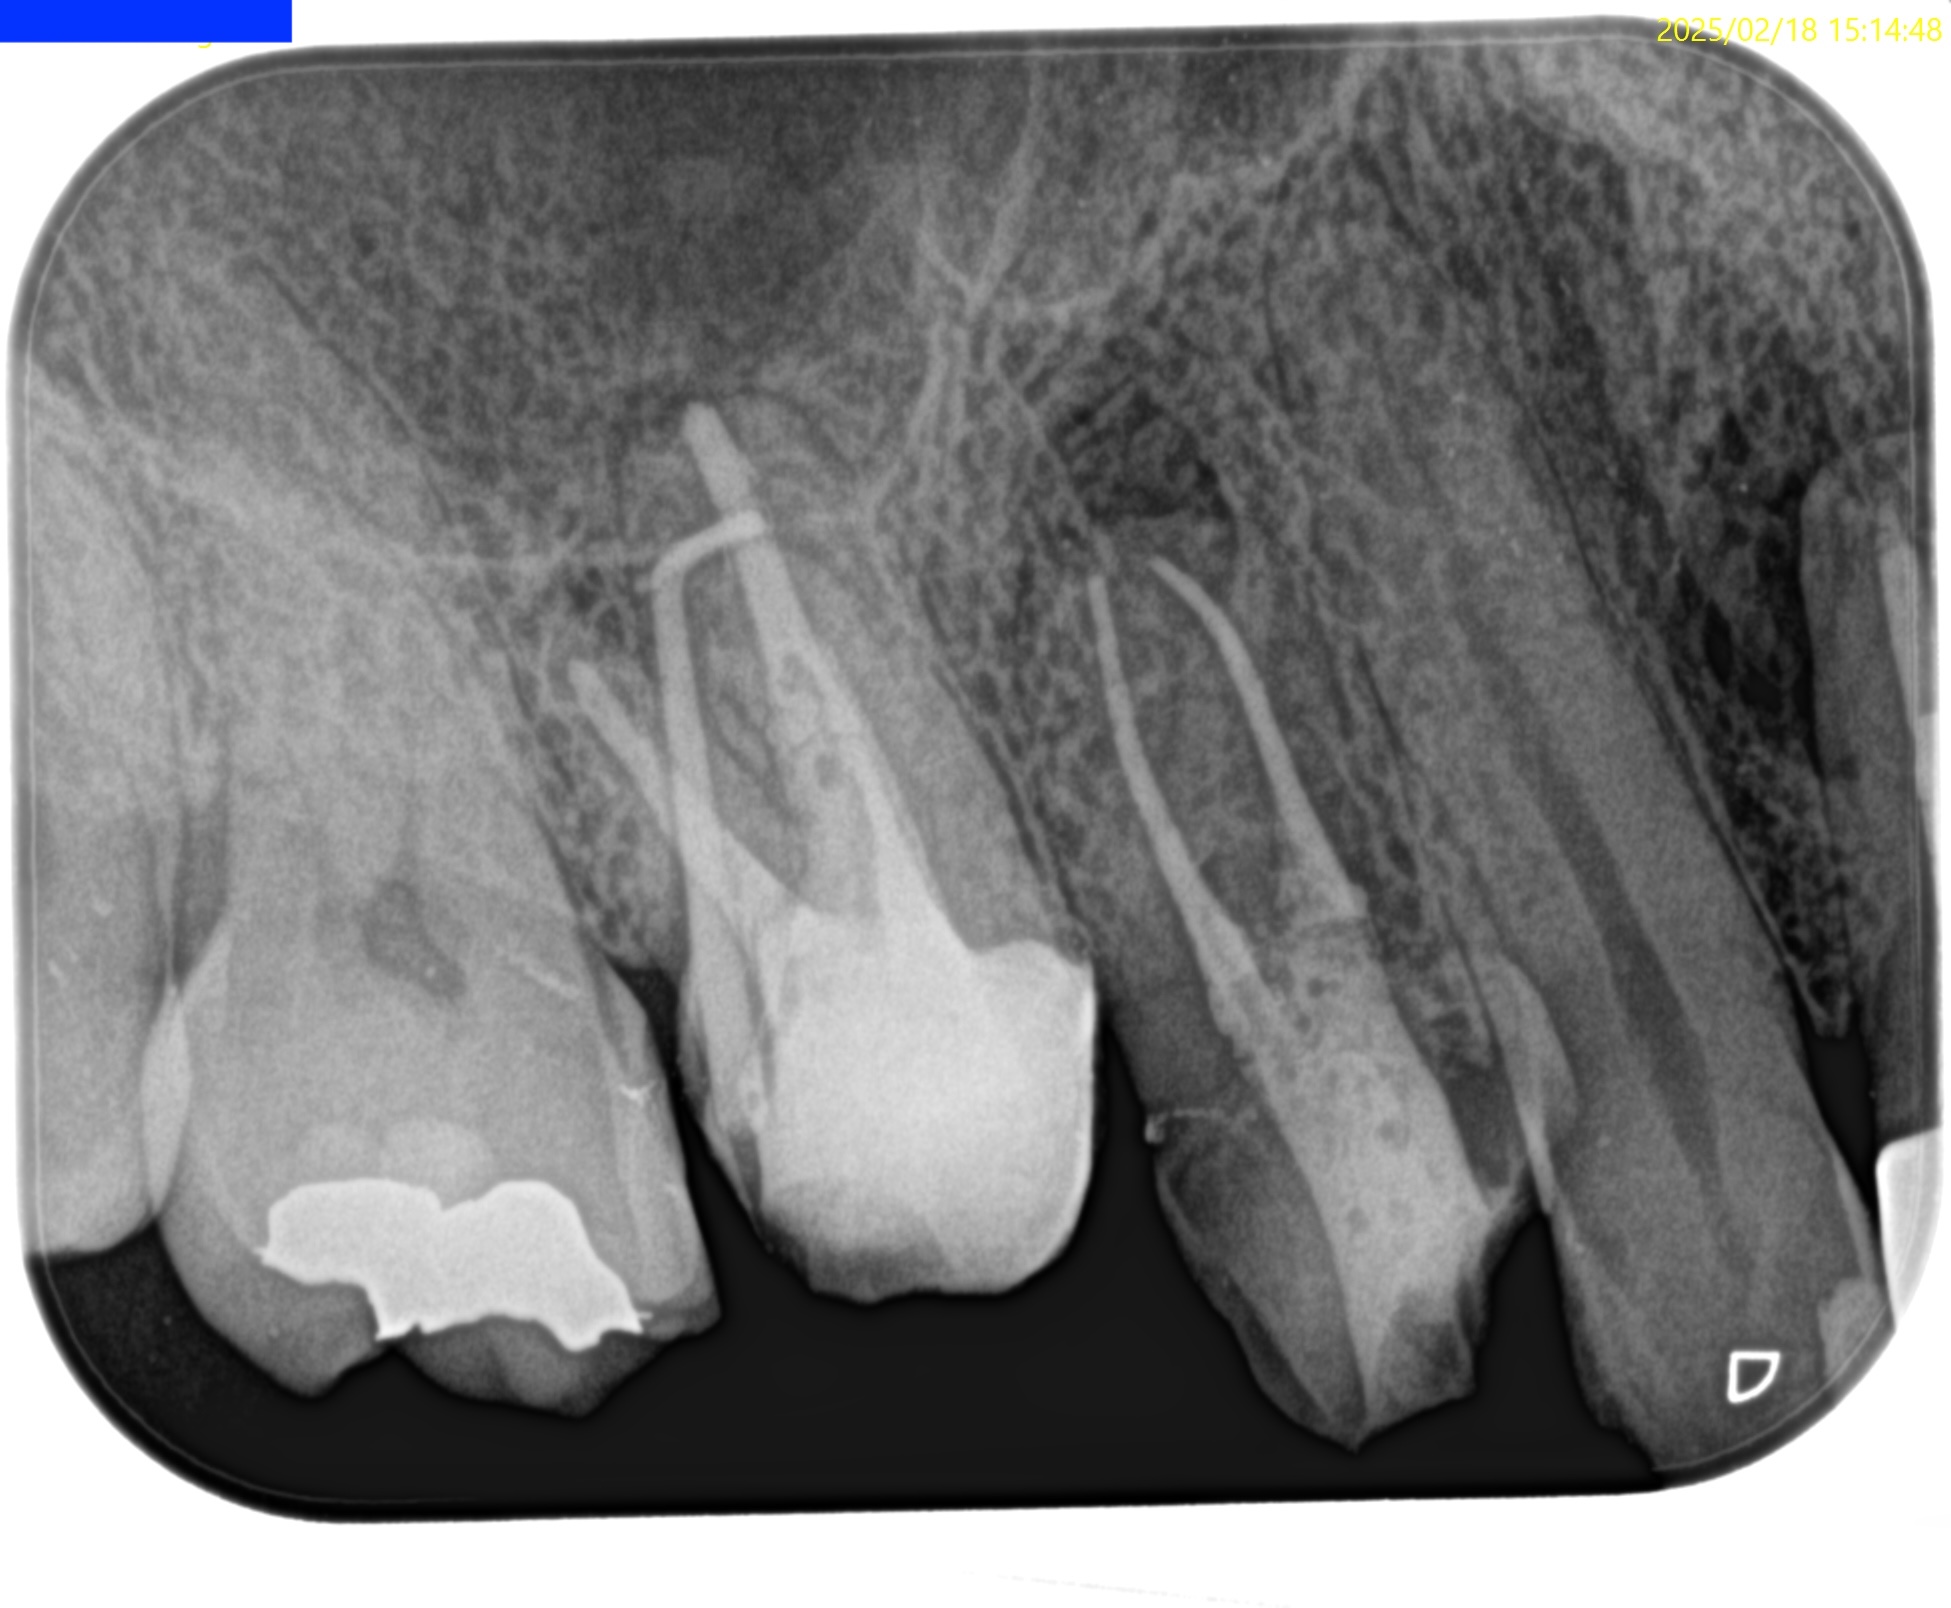

#3 MB Apicoectomy(2025.2.20)

#3 MBのApexは容易に発見できた。

このまま3mmで切断する。

その際は、頬舌的に4.5mm切断しなくてはならない。

大した距離ではないので容易だろう。

切断面は、

この形態と相似形なので問題はないだろう。

そして、この形態の中心にGutta Perchaが存在し、近傍にMB2があることが予想される。

頬舌的に超音波を動かさなくて済むのである。

かなりEasyだ。

ということで、逆根管形成した。

最後に逆根管充填した。

この時、シーラー

エンドセム MTA クイックペースト R

だけで逆根管充填している。

充填後、CBCTとPAを撮影した。

問題はないだろう。